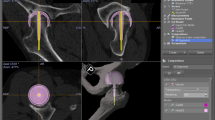

In the current CT-based navigation system, acetabular reaming and cup placement could be performed by checking the alignment and position in real time on the monitor. The positional navigation accuracy was, therefore, important, because surgeons could be informed of correct position of the implant in bone and thereby perform the operation safely. In a simulation, perforation of the acetabular wall could be observed when an acetabular cup was displaced 5-mm backward from the optimal position (Fig. 1). In such a case, the actual cup position in the bone should also be verified to confirm that perforation did not occur. One anatomical report showed that the minimum thickness of the medial acetabular wall in Crowe-I was an average of 3.8 ± 2.1 mm [34], suggesting that the acetabular bone stock is relatively thin and high positional accuracy is required to accurately display the cup position. The newer version group demonstrated within ± 3.1 mm of variation in any direction, while the older version group demonstrated within ± 5.7 mm of variation in any direction. This result indicates that safer surgery can be performed with trust of surgeons when the newer version navigation system is used. Standardization of treatment outcome can be expected by eliminating an error the navigation system.